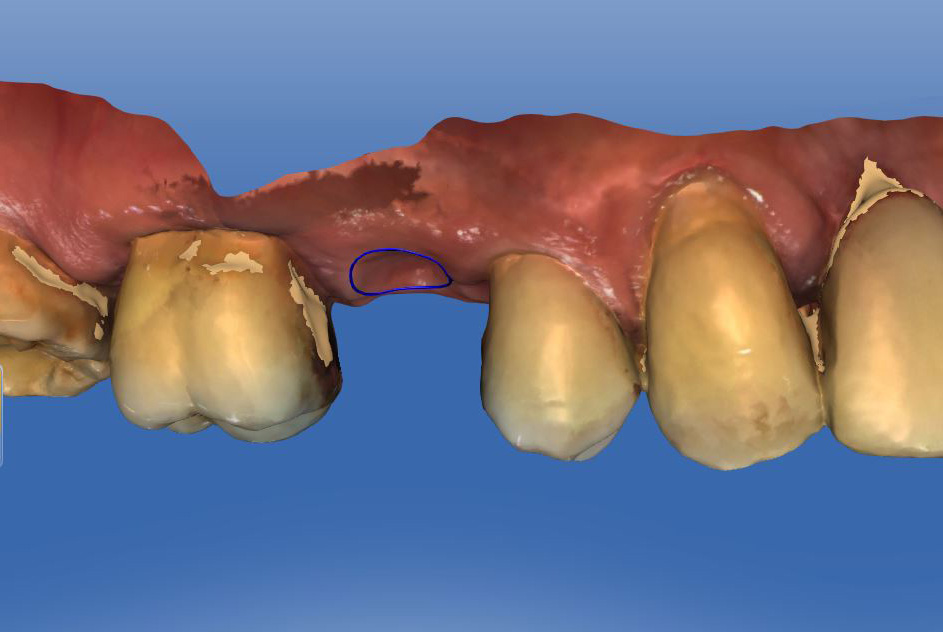

Ein 3D-Scan der Lücke mit dem Primescan und die virtuelle Planung des neuen Zahnes mit der CEREC-Software